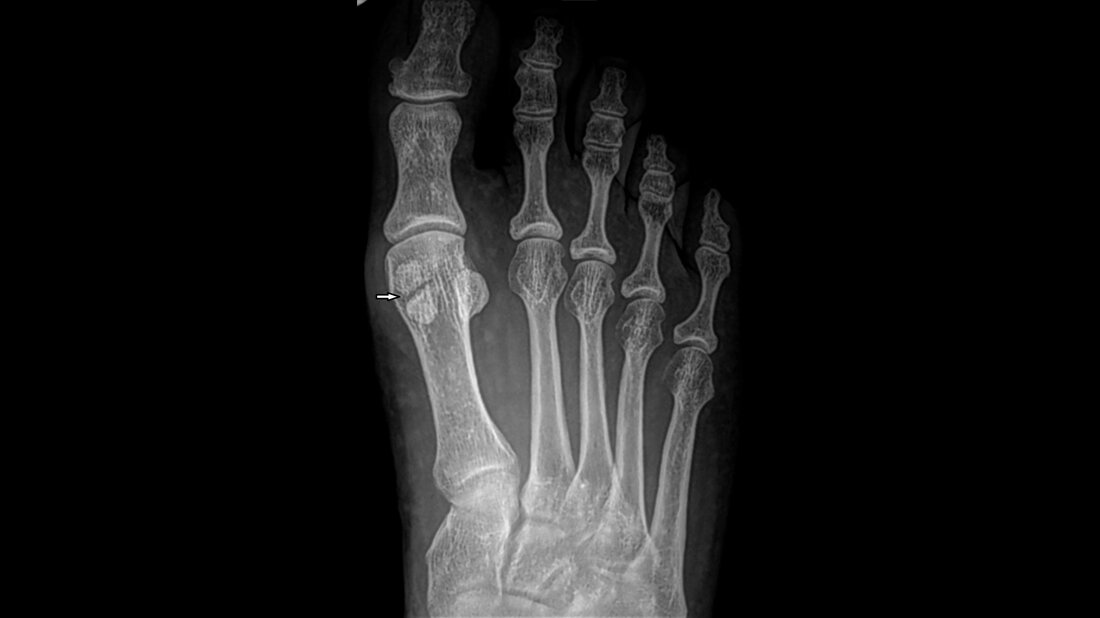

Anomalien und Normvarianten: Skelettale Veränderungen 3.31 – Varianz der Sesambeine des Vorfußes

Die Ossa sesamoidea des ersten Metatarsale zeigen eine spezielle anatomische Konfiguration. Lokale Schmerzen der Sesambeine können kongenitale, traumatische, arthritische, infektiöse und ischämische Ursachen haben. Die bildgebenden Möglichkeiten sind Röntgen, Computer- oder Kernspintomografie.

The sesamoid bones of the first metatarsal exhibit a special anatomic configuration. Painful conditions of the hallux sesamoid bones are many and include congenital, traumatic, arthritic, infectious, and ischemic conditions. The imaging examination include conventional radiography, computed tomography, or MRI.